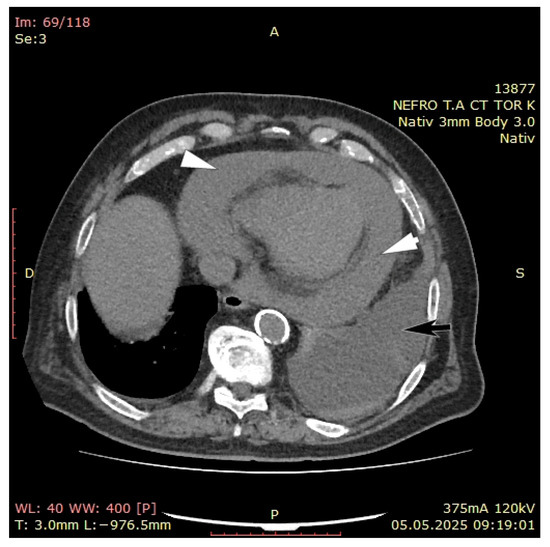

3. Case Presentation